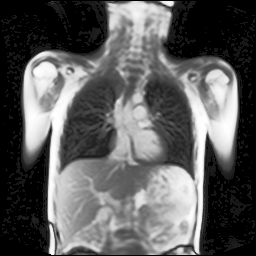

We trained our network on images of a 2D+t magnetic resonance (MR) image series of the lung. Due to the low proton density of the lung parenchyma in comparison to other body tissues as well as strong magnetic susceptibility effects, it is very challenging to acquire MR images with a sufficient signal-to-noise ratio. Recently, a novel MR pulse sequence called ultra-fast steady-state free precession (ufSSFP) was proposed [2]. ufSSFP allows detecting physiological signal changes in lung parenchyma caused by respiratory and cardiac cycles, without the need for intravenous contrast agents or hyperpolarized gas tracers. Multi-slice 2D+t ufSSFP acquisitions are performed in free-breathing.

Refer to captionRefer to captionRefer to captionRefer to captionRefer to captionRefer to captionRefer to captionRefer to captionRefer to captionRefer to captionRefer to captionRefer to captionRefer to captionRefer to caption

Figure 5: Maximum inspiration (top row) and maximum expiration (bottom row) for different slice positions of one patient from back to front.

For a complete chest volume coverage, the lung is scanned at different slice positions as shown in Figure 5. At each slice position, a dynamic 2D+t image series with 140 images is acquired. For the further analysis of the image data, all images of one slice position need to be spatially aligned. We choose the image which is closest to the mean respiratory cycle as fixed image of the series. The other images of the series are then registered to this image. Our data set consists of 48 lung acquisitions of 42 different patients. Each lung scan contains between 7 and 14 slices. We used the data of 34 patients for the training set, 4 for the evaluation set, and 4 for the test set.